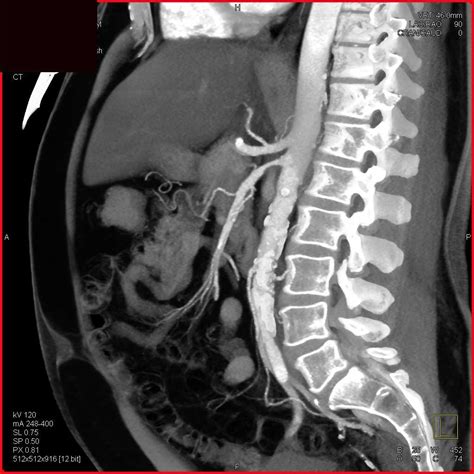

Diagnosis typically begins with a physical examination, followed by imaging studies. Physicians commonly utilize Duplex Ultrasound as a primary screening tool because it is non-invasive and effective at measuring blood velocity within the mesenteric arteries. More definitive imaging, such as a CT Angiography (CTA) or Magnetic Resonance Angiography (MRA), provides detailed, high-resolution views of the arterial anatomy, allowing surgeons to plan potential interventions.